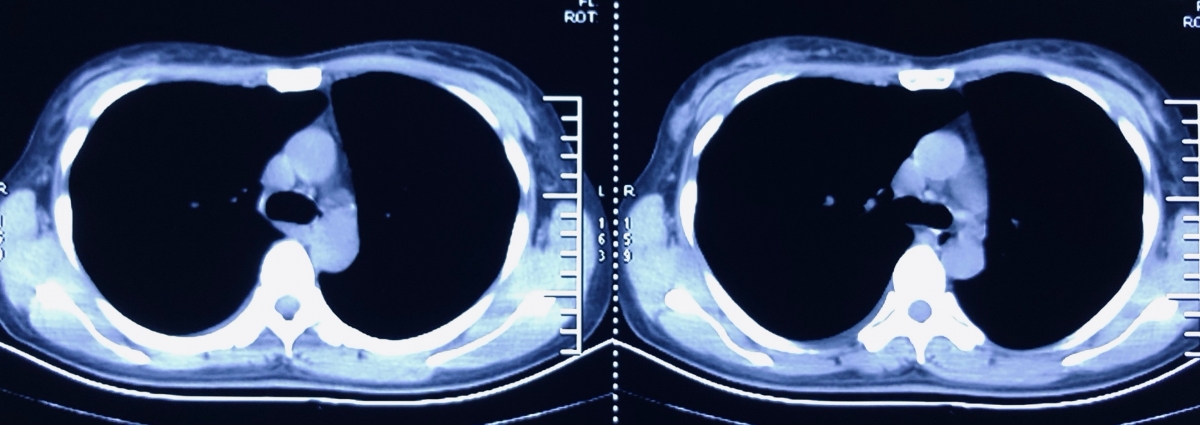

于1月21日受凉后开始出现咳嗽,无痰,无明显发热,至河北省中医院门诊查血常规:WBC 9.84×109/L N7.0×109/L L1.56×109/L,予以口服阿奇霉素0.25g/d 6天,咳嗽症状未见明显变化。2月6日咳嗽症状加重,咳黄痰,至社区卫生站就诊,查血常规:WBC 12.36×109/L N9.41×109/L L2.11×109/L,查胸片示:支气管炎、左肺结节、左下肺结节及条索,静点头孢呋辛、炎琥宁后2天,患者出现发热,体温最高37.6℃,咳嗽加重。2月9日再次因发热就诊于河北省中医院,发热门诊查血常规:WBC 6.1×109/L N 3.82×109/L L1.84×109/L,胸部CT示:双肺上叶少量炎症,双肺少量陈旧性病变,左下肺胸膜处占位。收入隔离病房观察,采咽试子查2次新冠病毒核酸阴性后,2月12日以“肺炎、左下肺占位”收入呼吸科病房单间继续治疗。

初始诊疗思路:肺炎按照2016成人CAP指南治疗,左下肺占位,片状密度增高,边界清晰,内部密度不均,伴钙化,无支气管影,需要鉴别肺炎、肺隔离症、肺肿瘤、肺不张等,胸部增强CT有助于通过特征征象鉴别上述疾病。

2月19日复查胸部增强CT:上叶病变同前,左肺下叶新磨玻璃影,炎症?左侧肺隔离症(左心房供血罕见)。